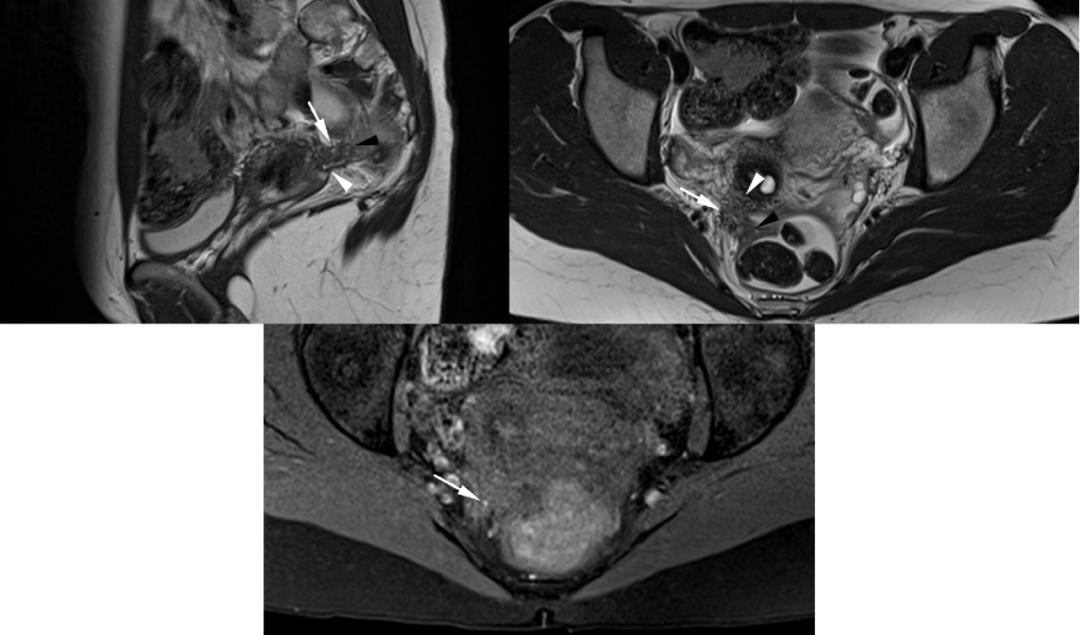

CASE 6

子宫内膜异位至右侧卵巢,T2WI 矢状位呈类圆形高信号,注意的是同时异位至道格拉斯窝及宫颈后区,T2WI 矢状位显示病灶呈低信号,中间夹杂更高信号结节,T1WI 轴位显示病灶多发高信号结节(提示多发出血点)